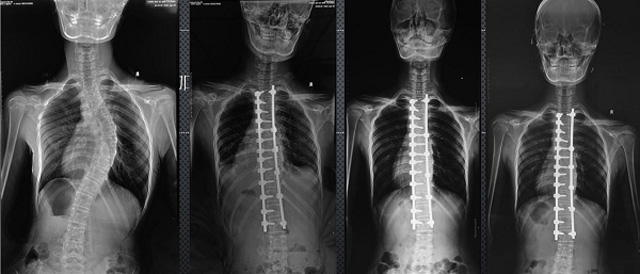

(7)全身拼接功能對有較大尺寸全脊柱拼接圖接桂成金下股分成幾次拍攝,再經過秋件開在骨科開展的全脊柱畸形矯治工作中,雖然CT. MRI也能獲取全脊柱影像,接圖像,以便于長度、角度、力線等測量和察脊柱在重力情況下但不能進行立位檢查,無法觀全景觀察。全身拼接功能是高等級DR攝取患者立位全下的功能狀態(tài)圖像,因此采用動態(tài)醫(yī)院特別看重的動態(tài)DR功能之一。注:圖中Cobb脊柱正側位圖像是首選的檢查方法角度的大小是反映側彎嚴重程度的一個標準。